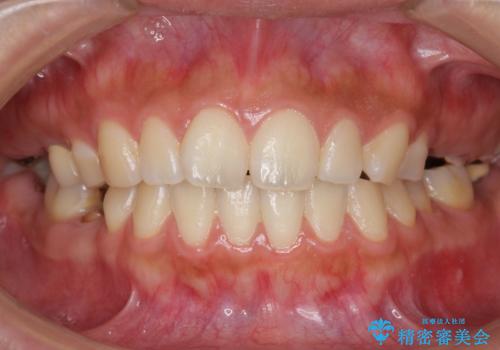

自家歯牙移植 使っていない親知らずを移植 20代女性

- う蝕により奥歯がボロボロになってしまい、咬むことができないことを主訴に来院された患者様です。

奥歯で咬むことができるようになり、また見た目も自然だと大変喜んで頂けました。